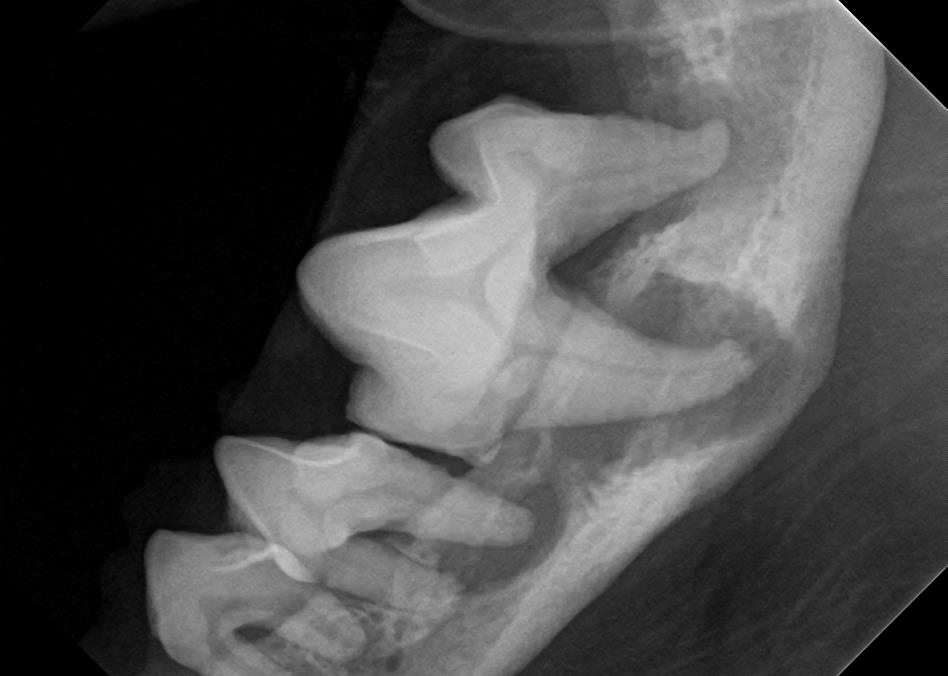

Dental X-Rays

Click on an image to learn more!